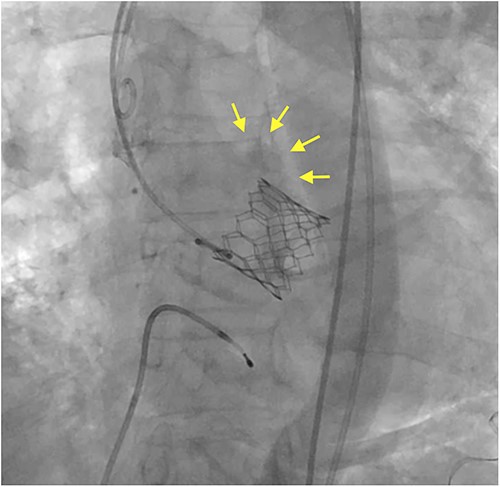

Under light sedation and local anesthesia, a 26-mm SAPIEN 3 valve was deployed with 1.5 ml less balloon inflation to avoid excessive pressure on the aortic annulus. After valve deployment, TTE revealed a small pericardial effusion. Pericardial drainage was performed, and blood was drained. Intraoperative angiography revealed a small amount of contrast leakage around the ascending aorta (Fig. 2). Transesophageal echocardiography (TEE) under deep sedation revealed a hematoma at the aortic annulus with blood inflow (Fig. 3a and b). Emergent open surgery was performed. The aorta was exposed through a median sternotomy. Cardiopulmonary bypass was established via the ascending aorta and the right atrium, and the aorta was cross-clamped. Antegrade cardioplegia was administered via an aortic root cannula, and cardiac arrest was achieved without complications. The prosthetic valve was firmly adherent to the aortic annulus and carefully removed. A tear in the non-left coronary commissure was sutured using 5–0 Prolene (Fig. 4). An INSPIRIS 21 mm valve (Edwards Lifesciences, Irvine, CA, USA) was implanted. The patient was discharged on postoperative day 14 after rehabilitation. One year after surgery, TTE revealed no paravalvular leakage and a preserved ejection fraction of 34%.

Intraoperative angiography shows a small contrast leakage at the ascending aorta (arrows).